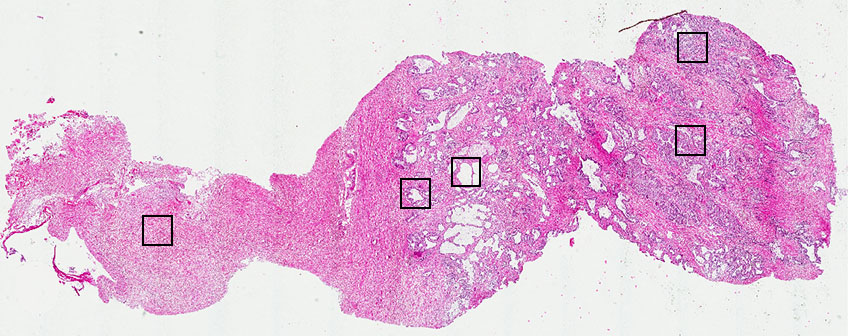

Glandular cells:

30

Smooth muscle cells:

65

Other cell types:

5